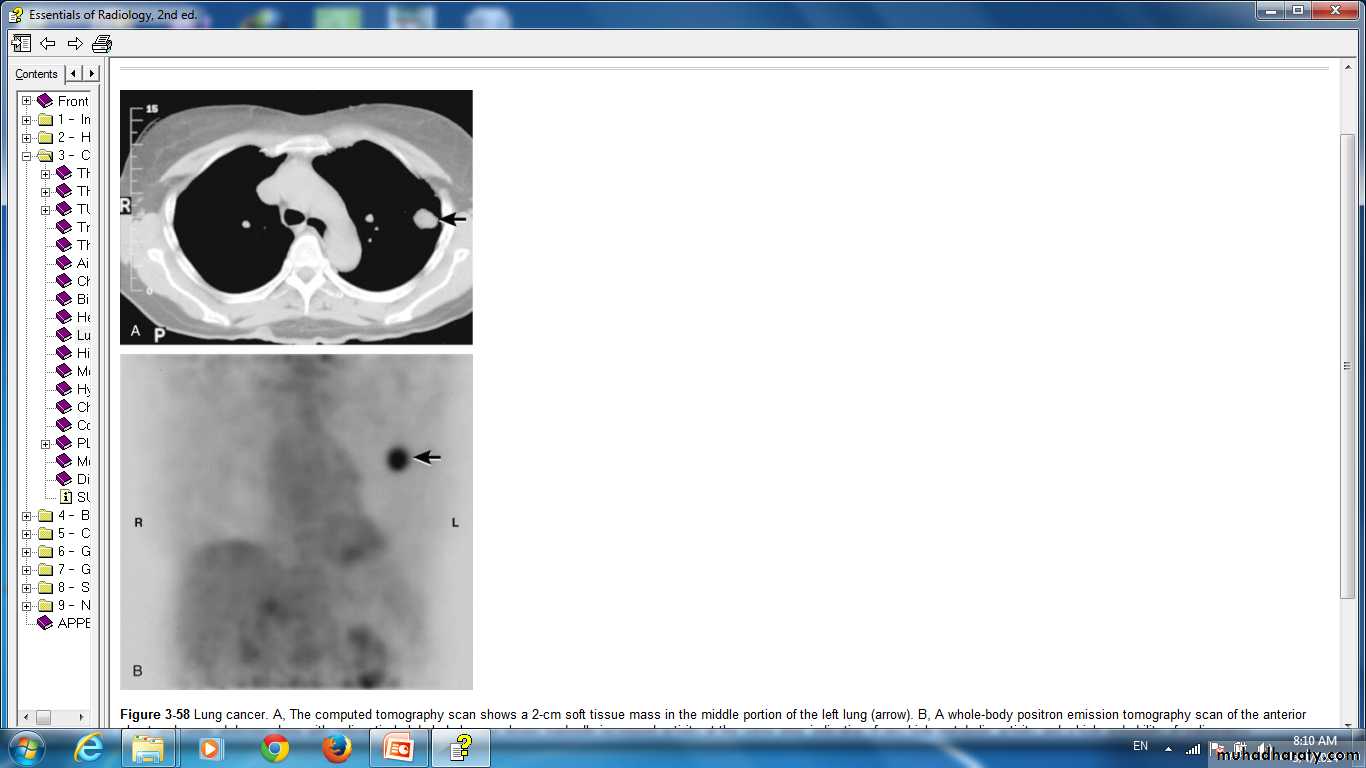

Lung cancer. A, The computed tomography scan shows a 2-cm soft tissue mass in the middle portion of the left lung (arrow). B, A whole-body positron emission tomography scan of the anterior chest and upper abdomen done with radioactively labeled glucose shows markedly increased activity at the same area, indicative of very high metabolic activity and a high probability of malignancy.

Lung cancer in right lung CT scan of thorax.

Lung cancer in right lung Positron emission tomography (PET) scan showing increased uptake in tumour